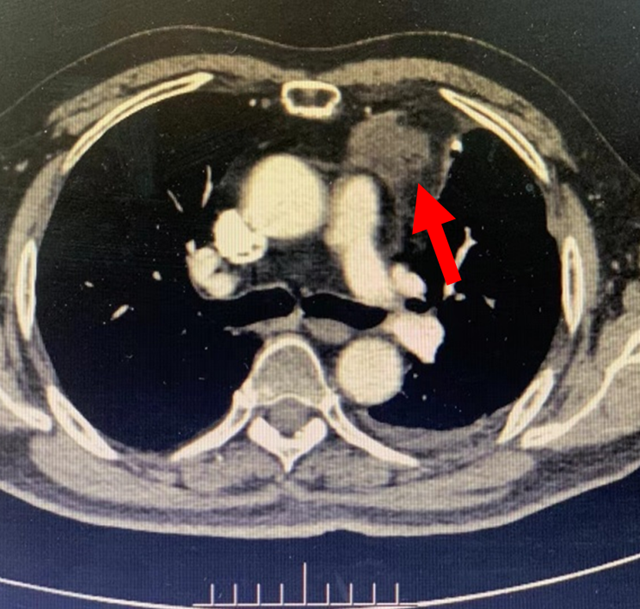

66岁的患者宋先生2年前因患前上纵隔胸腺鳞癌行胸腺癌切除加左肺上叶部分切除术,术后进行全量放疗和辅助化疗。1月前因胸痛,行胸部CT检查发现左前上纵隔软组织结节影,考虑为术后复发。

但由于患者基础疾病较多,合并高血压、2型糖尿病、冠心病等,癌肿与心脏大血管关系紧密,加之患者手术和术后辅助放疗引起胸腔及病灶周围严重粘连,不适合再次手术和放疗。

术前增强CT扫描